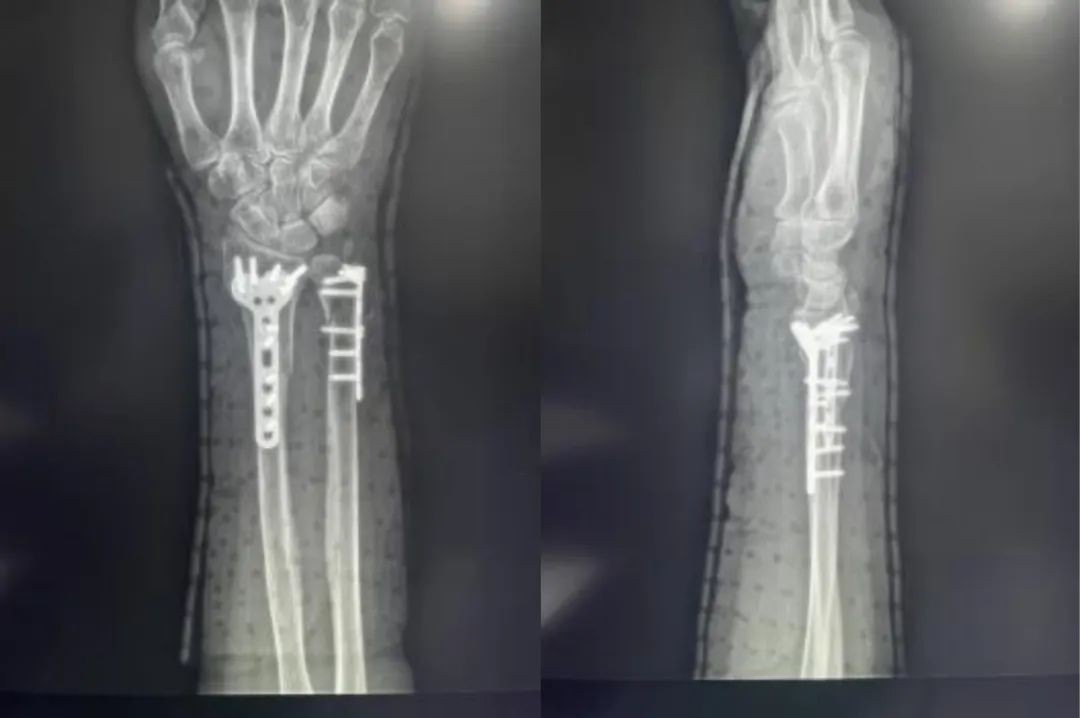

Primer ①